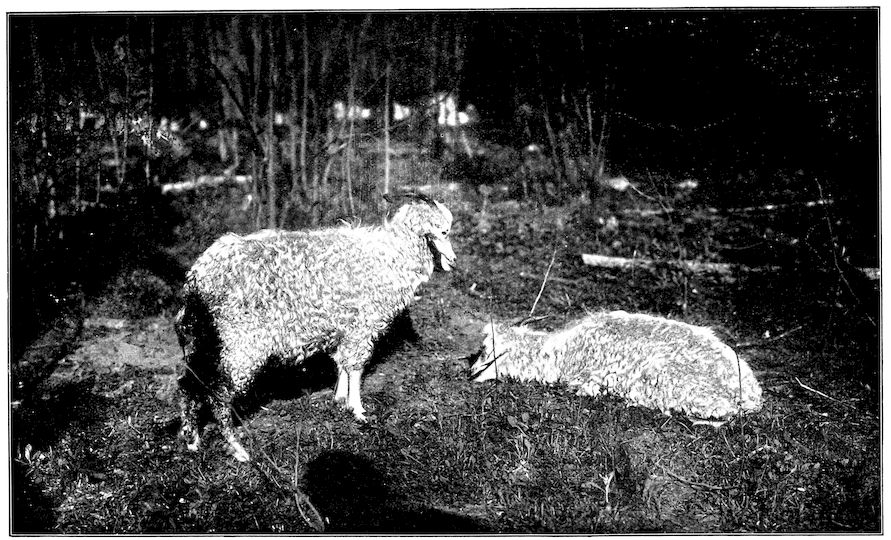

| “Trembling,” or Lumbar prurigo, in sheep | 475 | |||

| Louping-ill | 429 | |||

| Suggested measures for prevention | 435 | |||